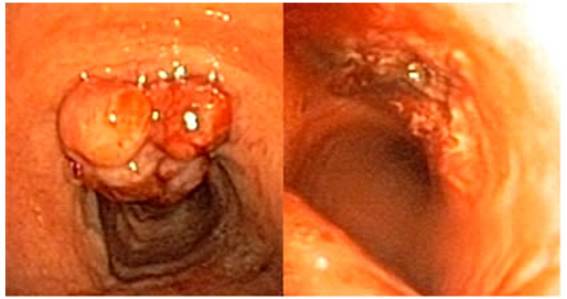

En

dicha broncoscopia, se observó un

nódulo mamelonado irregular de crecimiento exofítico

en la cara anterior de la tráquea a dos centímetros de las

cuerdas vocales, que presentaba signos de sangrado reciente, pero sin sangrado

activo en el momento de la exploración. A pesar de la lesión, la

tráquea presenta una luz libre del 70%.

Al

explorar de nuevo la tráquea del paciente, se observó un aumento

claro del tamaño de la lesión. La biopsia transcurre sin

incidencias y se envían muestras al laboratorio de anatomía

patológica del hospital. Tras la vaporización de la

lesión, queda una luz traqueal del 100%, con buen resultado

macroscóÂpico. El paciente no presentaba signos de compresión

extrínseca ni colapso dinámico de la vía aérea.